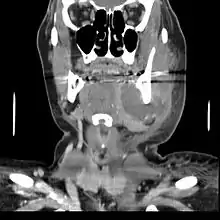

A dental infection resulting in an abscess and inflammation of the maxillary sinus

CT scan showing a large tooth abscess (right in the image) with significant inflammation of fatty tissue under the skin

If left untreated, a severe tooth abscess may become large enough to perforate bone and extend into the soft tissue eventually becoming osteomyelitis and cellulitis respectively. From there it follows the path of least resistance and may spread either internally or externally. The path of the infection is influenced by such things as the location of the infected tooth and the thickness of the bone, muscle and fascia attachments.